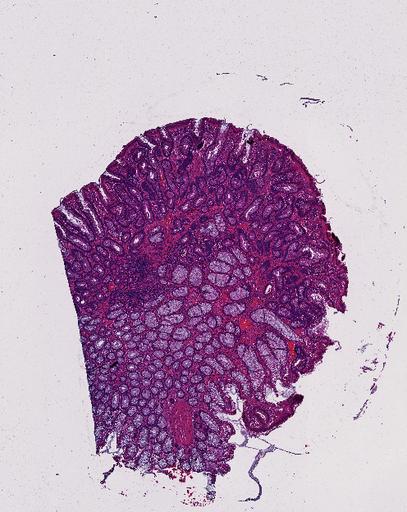

High‑resolution three‑dimensional (3D) tissue atlases promise to redefine how we study cellular architecture‑function relationships in human tissues. Large-scale consortia such as the Human Bimolecular Atlas Program (HuBMAP) systematically build detailed 3D organ maps by profiling serial tissue sections with single-cell spatial technologies. However, an accurate and efficient reconstruction method that can handle atlas-scale datasets remains elusive. We introduce Space-map, an open-source method that integrates single‑cell coordinates with optional histological image features to assemble serial sections into 3D models. Space‑map combines multi‑scale feature matching with large‑deformation diffeomorphic metric mapping, delivering global reconstructions while preserving local micro‑anatomy. To demonstrate the capability of Space-map, we generated a serially sectioned spatial transcriptomics (Xenium, ~2.9M cells) dataset and a spatial proteomics dataset (CODEX, ~2.4M cells). Applying Space-map to these single-cell spatial maps, we built three 3D models for both diseased (colon polyp) and reference colon tissues. These high-resolution 3D models showcase the intricate structure of the human colon across different states. Space-map is fast and highly efficient. We demonstrated its performance and accuracy using in‑house and public datasets. The result shows that Space‑map is 10 times faster and ~2‑fold more accurate than PASTE and STalign, making 3D atlas reconstruction more accessible. Our study provides a new robust and user-friendly software available at https://github.com/a12910/spacemap that can be easily applied for constructing molecular 3D tissue maps of human organs at single-cell resolution.